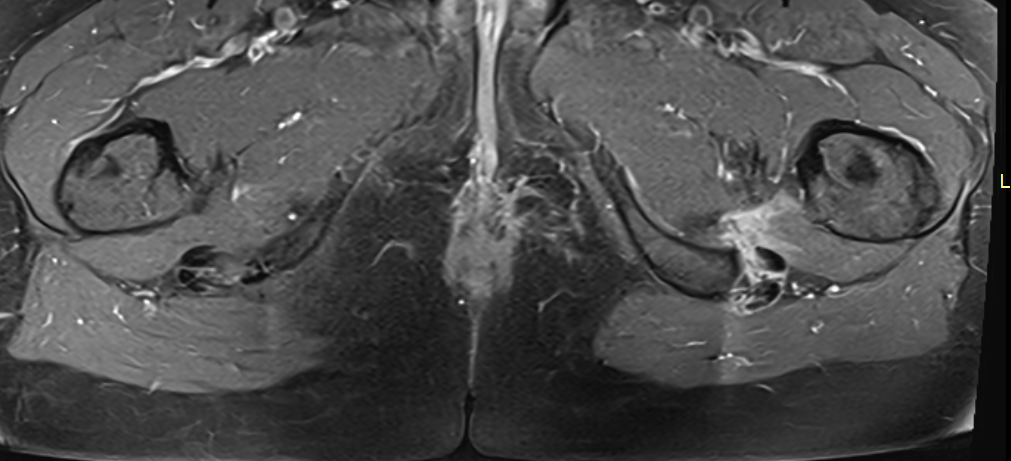

5. Redukcja przestrzeni kulszowo-udowej – rzadsza, ale istotna przyczyna bólu biodra

Redukcja przestrzeni kulszowo-udowej (konflikt kulszowo-udowy) to najrzadsza, a jednocześnie najbardziej problematyczna diagnostycznie przyczyna bólu biodra. Dolegliwości mają często nietypowy charakter i mogą imitować rwę kulszową lub bóle mięśniowe.

Typowe cechy kliniczne:

• głęboki ból pośladka,

• promieniowanie do tylnej części uda,

• nasilenie dolegliwości przy wyproście biodra.

Standardowe badania obrazowe często nie wykazują jednoznacznych zmian, co sprawia, że pacjenci przez długi czas pozostają bez właściwego rozpoznania.

❓ Dlaczego redukcja przestrzeni kulszowo-udowej jest trudna do rozpoznania?

Redukcja przestrzeni kulszowo-udowej jest rzadka i daje niespecyficzne objawy, często przypominające rwę kulszową lub bóle mięśniowe. Standardowe badania obrazowe mogą nie wykazywać jednoznacznych zmian, dlatego schorzenie to bywa długo nierozpoznane.